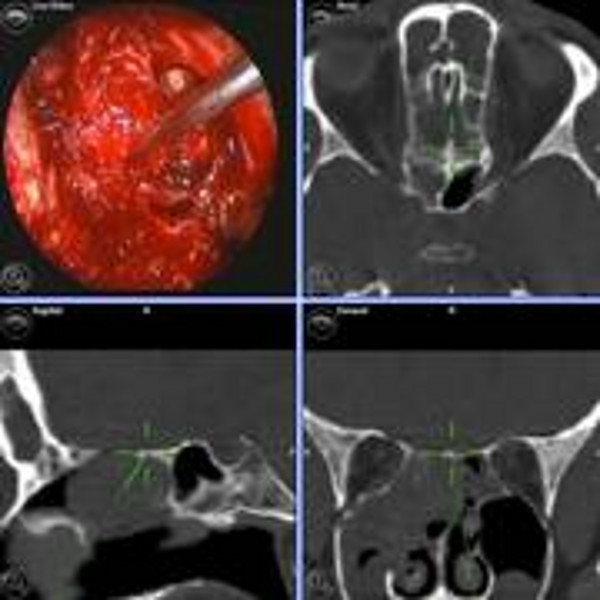

Karzinome der Nase, der Nasennebenhöhlen (NNH) und der Frontobasis können sich aus unterschiedlichen Geweben entwickeln und weisen so auch eine größere feingewebliche Varianz und ein unterschiedliches Wachstums- und Metastasierungsverhalten auf. Zu den häufigsten bösartigen Tumorarten rechnet man das Plattenepithelkarzinom, das anaplastische Karzinom, das Adenokarzinom oder das adenoidzystische Karzinom. Es gibt allerdings eine große Anzahl varianter Tumore, die sich in der Nase, den Nasennebenhöhlen oder der Schädelbasis ausbreiten können. Ihnen gemeinsam ist die Möglichkeit, sich nicht nur auf das Nasen- und Nasennebenhöhlensystem zu beschränken, sondern möglicherweise benachbarte Strukturen, wie die Augenhöhle oder die Hirnhäute und das Gehirn zu infiltrieren.